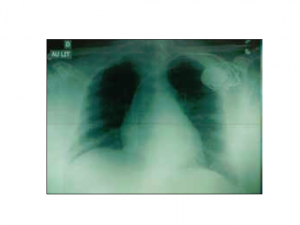

Atrophie cérébrale bi-frontale inhabituelle, à quoi peut-elle être due ?

Cas clinique : Mme B., âgée de 74 ans, est hospitalisée en unité de médecine aiguë gériatrique pour sepsis sévère sur pneumonie à Streptococcus pneumoniae. Cette patiente a des antécédents…